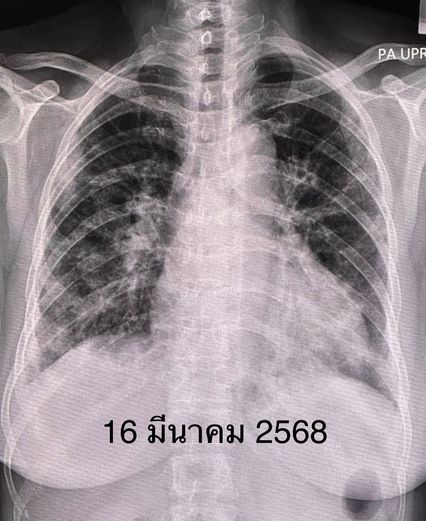

เจาะเลือด พบเลือดจางเล็กน้อย ค่าอักเสบในเลือด ESR และ hs-CRP สูง, ANA ปกติ ค่าโซเดียมในเลือดต่ำ เอกซเรย์ปอดและคอมพิวเตอร์ปอดพบปอดอักเสบทั้ง 2 ข้าง แยงจมูก ส่งเลือดเพาะเชื้อ ส่องกล้องเข้าไปในหลอดลม ไม่พบการติดเชื้อแบคทีเรีย ไวรัส เชื้อรา หรือวัณโรค ได้ยาปฏิชีวนะ เอกซเรย์ปอดซ้ำไม่ดีขึ้น หลังรักษาที่โรงพยาบาลใกล้บ้าน 26 วัน ญาติขอย้ายมารักษาต่อวันที่ 11 เม.ย.68

วันที่ย้ายมา หลังจากซักประวัติ ตรวจร่างกาย และทบทวนประวัติเดิม คิดถึงโรคภูมิต้านทานตนเอง (Autoimmune Diseases) ทำให้เกิดโรคเนื้อเยื่อปอดอักเสบ หรือ Interstitial lung disease (ILD) มากที่สุด ส่งเลือดตรวจพบ Anti MDA5 และ Anti-Ro52 บวก ค่า Ferritin สูง ค่า CPK ของกล้ามเนื้อปกติ ค่าเอนไซม์ของตับสูงเล็กน้อย ค่าไตปกติ ระดับโซเดียมในเลือดต่ำเกิดจาก Syndrome of inappropriate ADH (SIADH)

วินิจฉัยว่า ผู้ป่วยรายนี้เป็นโรคภูมิต้านทานตัวเองชนิด Anti-MDA5 antibody positive dermatomyositis ทำให้เนื้อเยื่อปอดอักเสบ และปอดเกิดพังผืดอย่างรวดเร็ว ไม่มีกล้ามเนื้ออ่อนแรง ไม่มีความผิดปกติของผิวหนังให้ยาสเตียรอยด์ชนิดฉีดขนาดสูง ต่อมาเปลี่ยนเป็นชนิดกิน ยากดภูมิคุ้มกันไมโคฟีโนเลต (mycophenolate) ยาไฮดรอกซีคลอโรควิน (hydroxychloroquine) และยา Tolvaptan รักษาโรคโซเดียมในเลือดต่ำ

หลังได้รับยา คนไข้เหนื่อยน้อยลง ระดับออกซิเจนที่ปลายนิ้วดีขึ้น ใช้ออกซิเจนแบบหนวดกุ้งธรรมดาทางจมูก ไม่ต้องใช้ High-Flow nasal O2 cannula เอกซเรย์ปอดดีขึ้นช้า ๆ ลุกขึ้นเดินได้ ระดับโซเดียมในเลือดเกือบปกติ กลับบ้านได้หลังจากรักษาอยู่ในโรงพยาบาล 15 วัน หมอนัดติดตามเป็นคนไข้นอกต่อไป